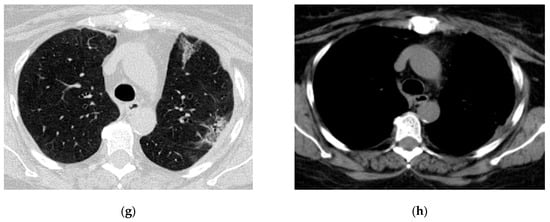

Figure 5.

Radiologic evolution of case 3: Axial chest CT scans after first percutaneous ICD insertion revealing insufficient drainage of the purulent cavity; pleural effusion with few air inclusions; right ICD and diffuse interstitial infiltrates (a,b). In this case, multiple drainage and drain revisions were necessary to optimally control the purulent infection. Smaller right residual cavity with stable pleural effusion after ICD revision (c,d). Chest CT scans 1-month follow-up show the Foley catheter and decreasing size of the residual cavity (e). A follow-up CT scan after ICD removal showed small residual pleural and pulmonary fibrotic changes (f).